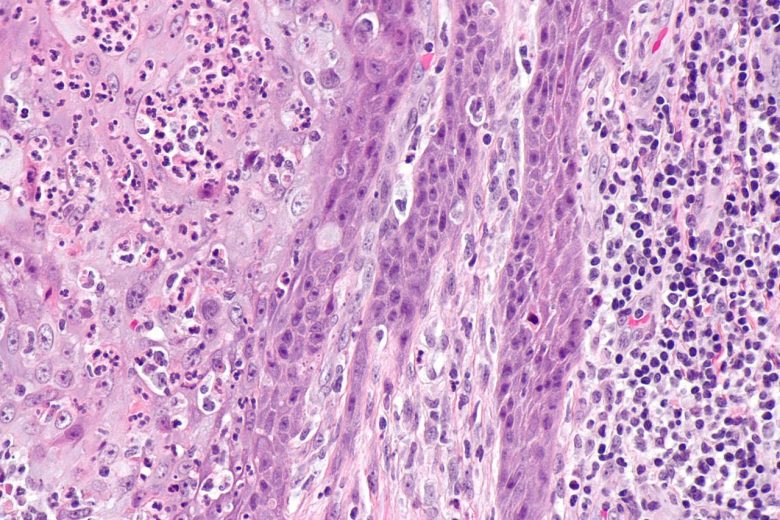

Esophageal cancer

“The most common types of esophageal cancer are adenocarcinoma and squamous cell carcinoma. These two forms of esophageal cancer tend to develop in different parts of the esophagus and are driven by different genetic changes.

“Smoking, heavy alcohol use, and Barrett esophagus can increase the risk of esophageal cancer. Signs and symptoms of esophageal cancer are weight loss and painful or difficult swallowing. Tests that examine the esophagus are used to detect (find) and diagnose esophageal cancer.”